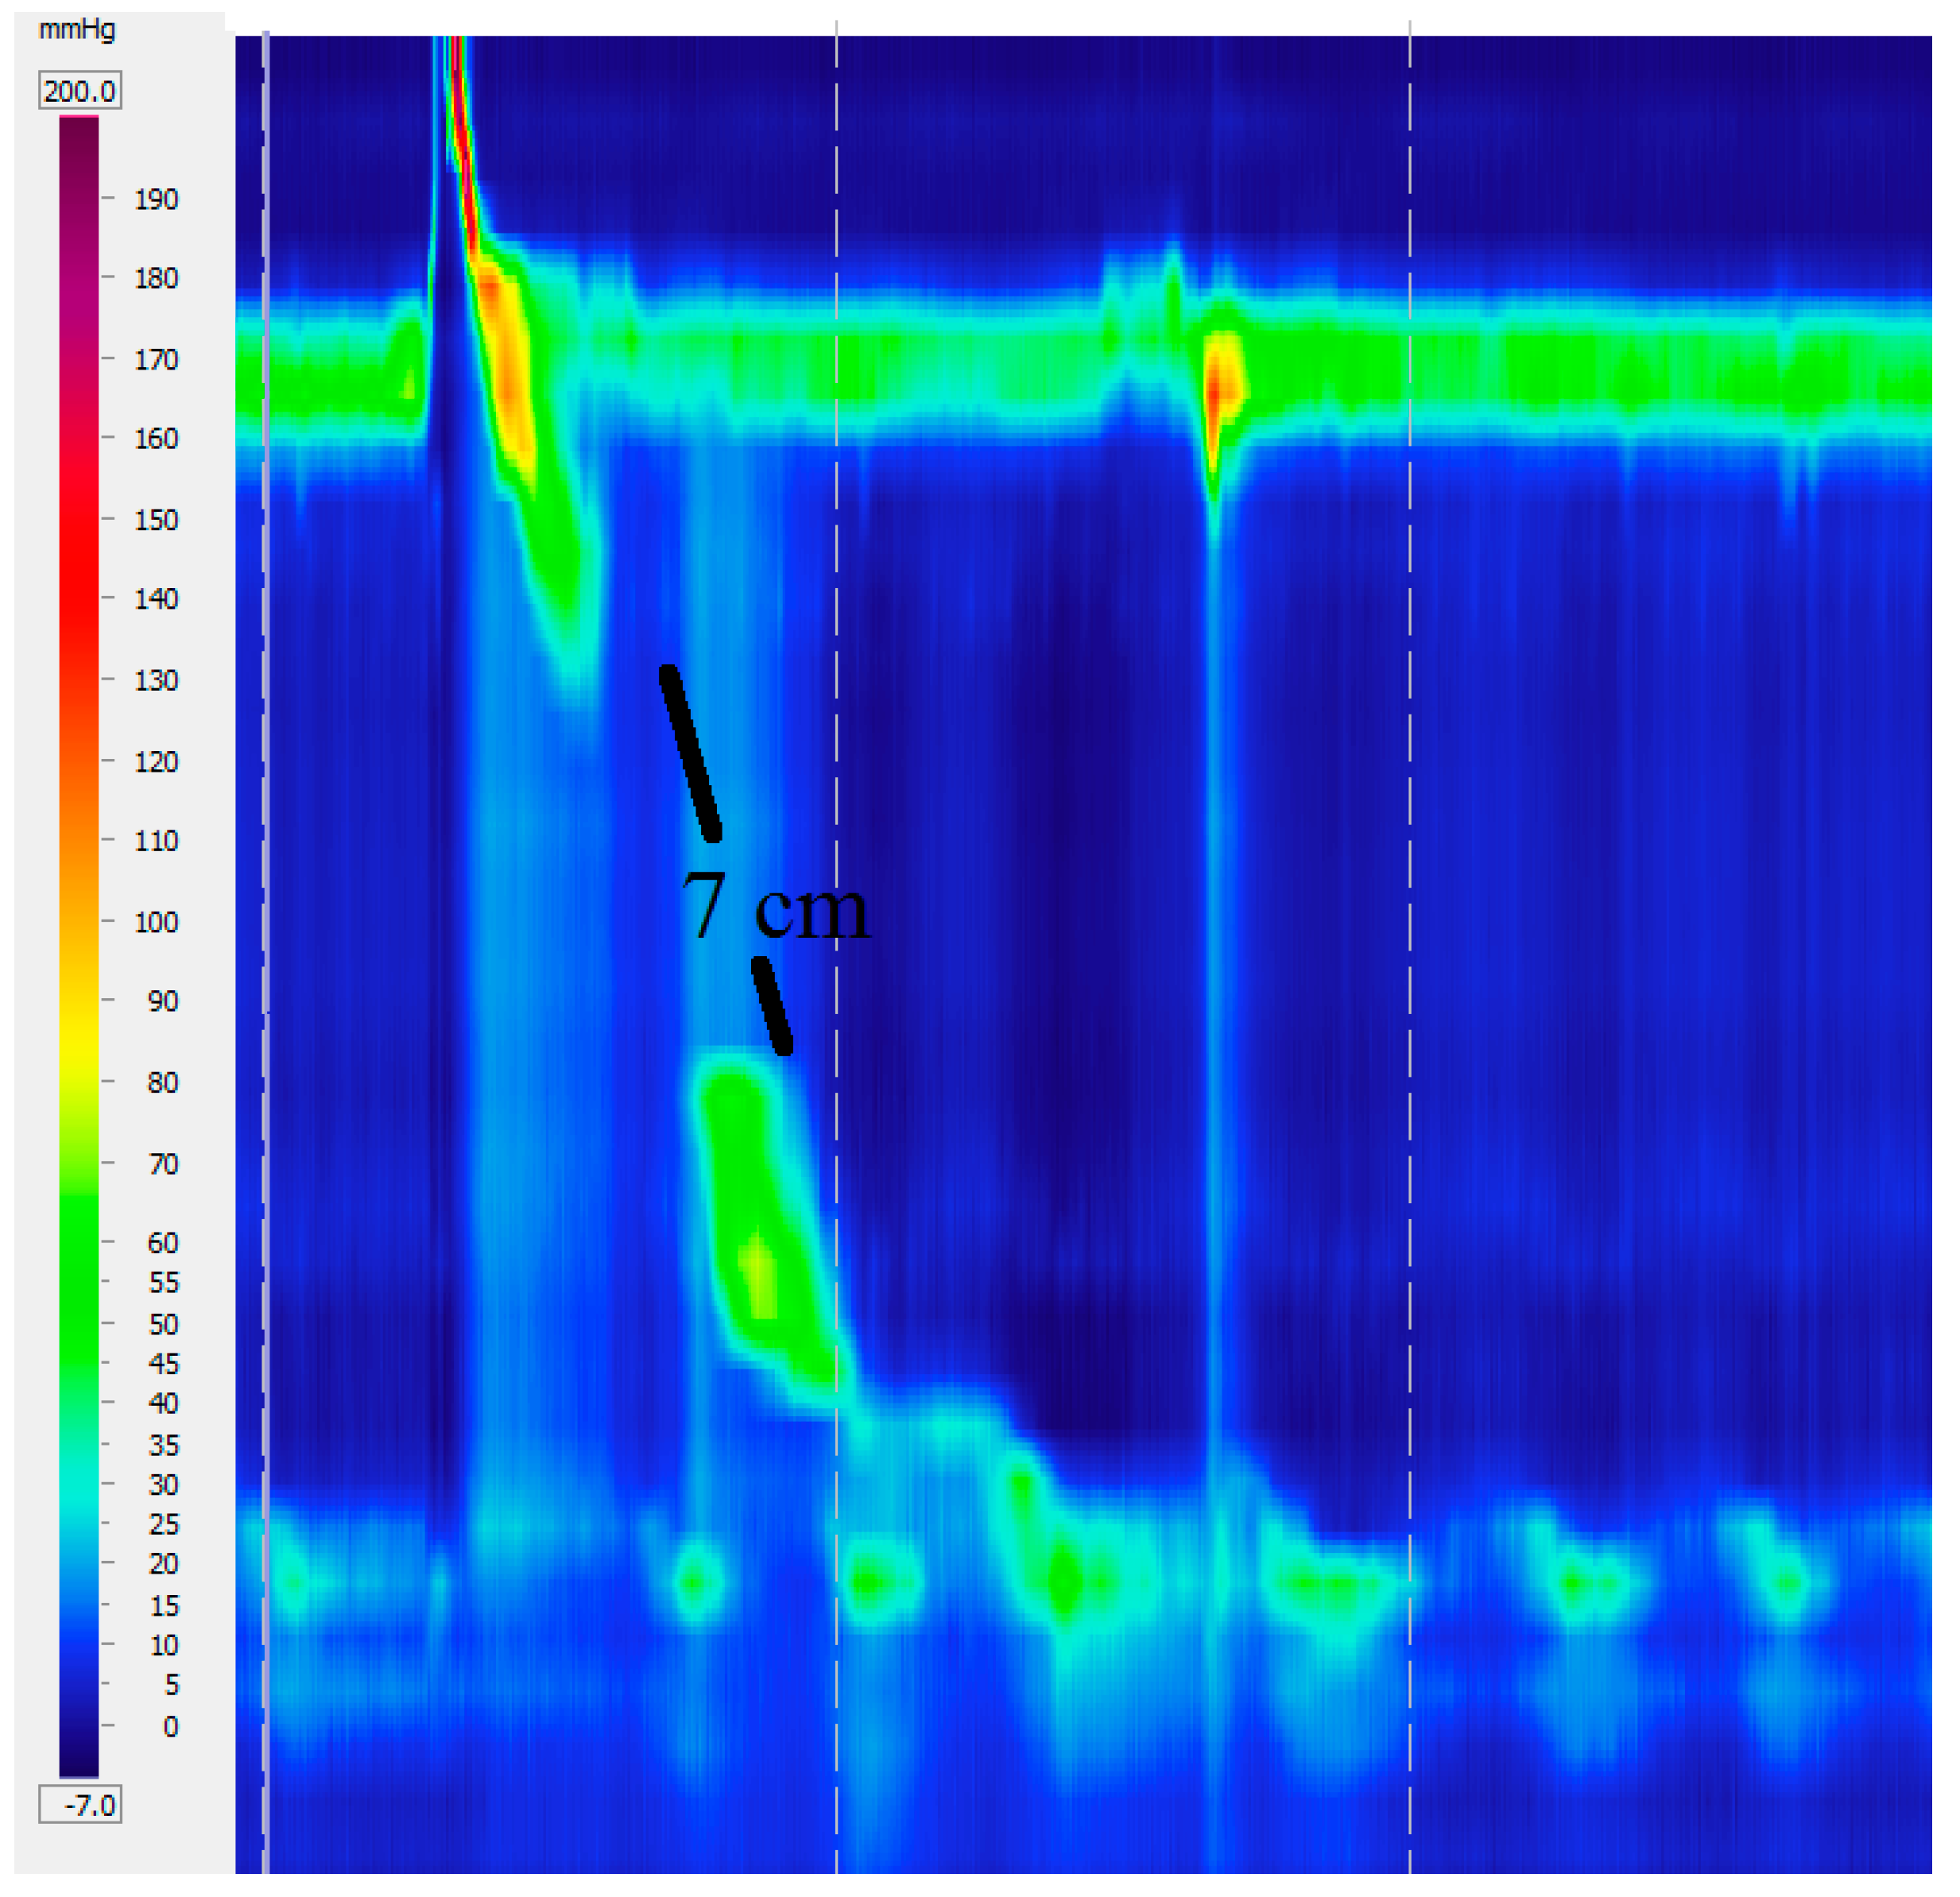

4.1. Distal Esophageal Spasm